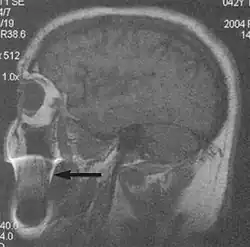

Fig. 1. Motion artifact (T1 coronal study of cervical vertebrae).[1]

A motion artifact is one of the most common artifacts in MR imaging.[2] Motion can cause either ghost images or diffuse image noise in the phase-encoding direction. The reason for mainly affecting data sampling in the phase-encoding direction is the significant difference in the time of acquisition in the frequency- and phase-encoding directions.[1] Frequency-encoding sampling in all the rows of the matrix (128, 256 or 512) takes place during a single echo (milliseconds). Phase-encoded sampling takes several seconds, or even minutes, owing to the collection of all the k-space lines to enable Fourier analysis. Major physiological movements are of millisecond to seconds duration and thus too slow to affect frequency-encoded sampling, but they have a pronounced effect in the phase-encoding direction. Periodic movements such as cardiac movement and blood vessel or CSF pulsation cause ghost images, while non-periodic movement causes diffuse image noise (Fig. 1). Ghost image intensity increases with amplitude of movement and the signal intensity from the moving tissue. Several methods can be used to reduce motion artifacts, including patient immobilisation, cardiac and respiratory gating, signal suppression of the tissue causing the artifact, choosing the shorter dimension of the matrix as the phase-encoding direction, view-ordering or phase-reordering methods and swapping phase and frequency-encoding directions to move the artifact out of the field of interest.[1]